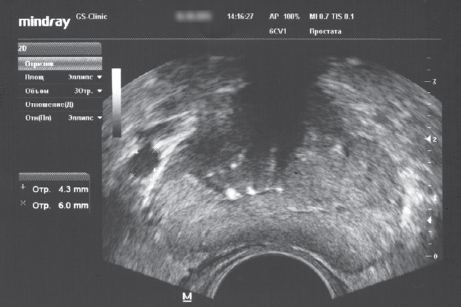

В 2006 г. нами впервые был введен термин «рено-пельвикальный венозный анастомоз» для описания процесса перераспределения венозной крови у больных с левосторонним варикоцеле при артериальном аортомезентериальном пинцете из бассейна левой почечной вены (через венозный анастомотический узел, образованный v. testicularis interna sinistra, v. ductus deferens sinistra и v. cremasterica sinistra) в венозный бассейн v. pudenda interna и plexus venosus prostaticus (рис. 2). Это позволило предположить, что варикоцеле выступает гемодинамической предпосылкой развития венозного полнокровия органов малого таза и рецидивирования хронического простатита (рис. 3) [21].

Рис. 3. Трансректальное ультразвуковое исследование простаты пациента Л., 69 лет, с левосторонним варикоцеле 2-й стадии. Объем простаты — 16,5 см3. Максимальный диаметр вен слева — 6,0 мм. Хронический калькулезный простатит

Fig. 3. Transrectal ultrasound of the prostate of patient L., 69 years old, with left-sided varicocele stage 2. The volume of the prostate is 16.5 cm3. The maximum diameter of the veins on the left is 6.0 mm. Chronic calculous prostatitis